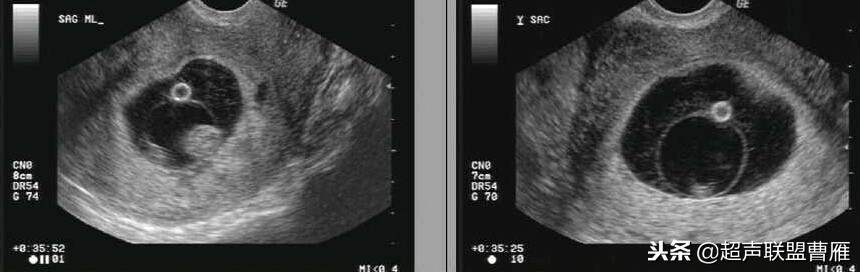

正常早孕卵黄囊声像图

早孕 胚芽 卵黄囊

5周+ 、6周+ 声像图

孕7周左右(胚芽11mm 卵黄囊)

胎芽 卵黄囊 心管搏动信号

宫内早孕 (7周左右)

正常宫内胚胎组织、卵黄囊